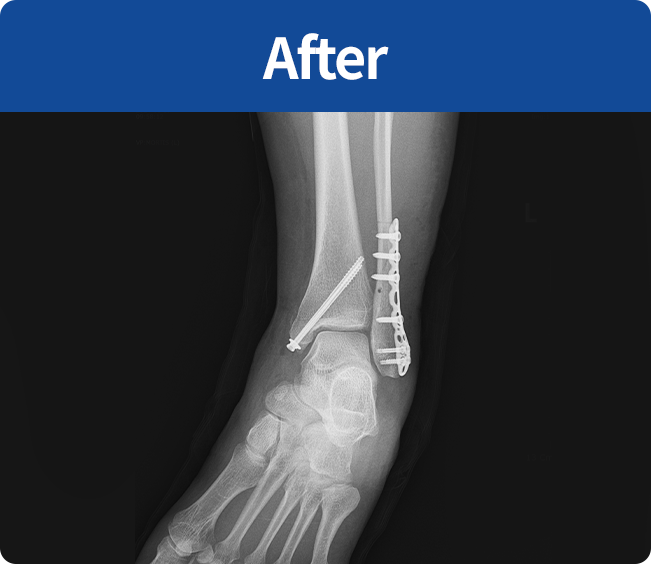

골절 고정술

부러진 뼈를 해부학적 위치로 정확하게 맞춘 뒤,

뼈가 안정적으로 붙을 수 있도록 금속판, 나사, 핀 등을 이용해 고정하는 수술

(내고정술, 외고정술)